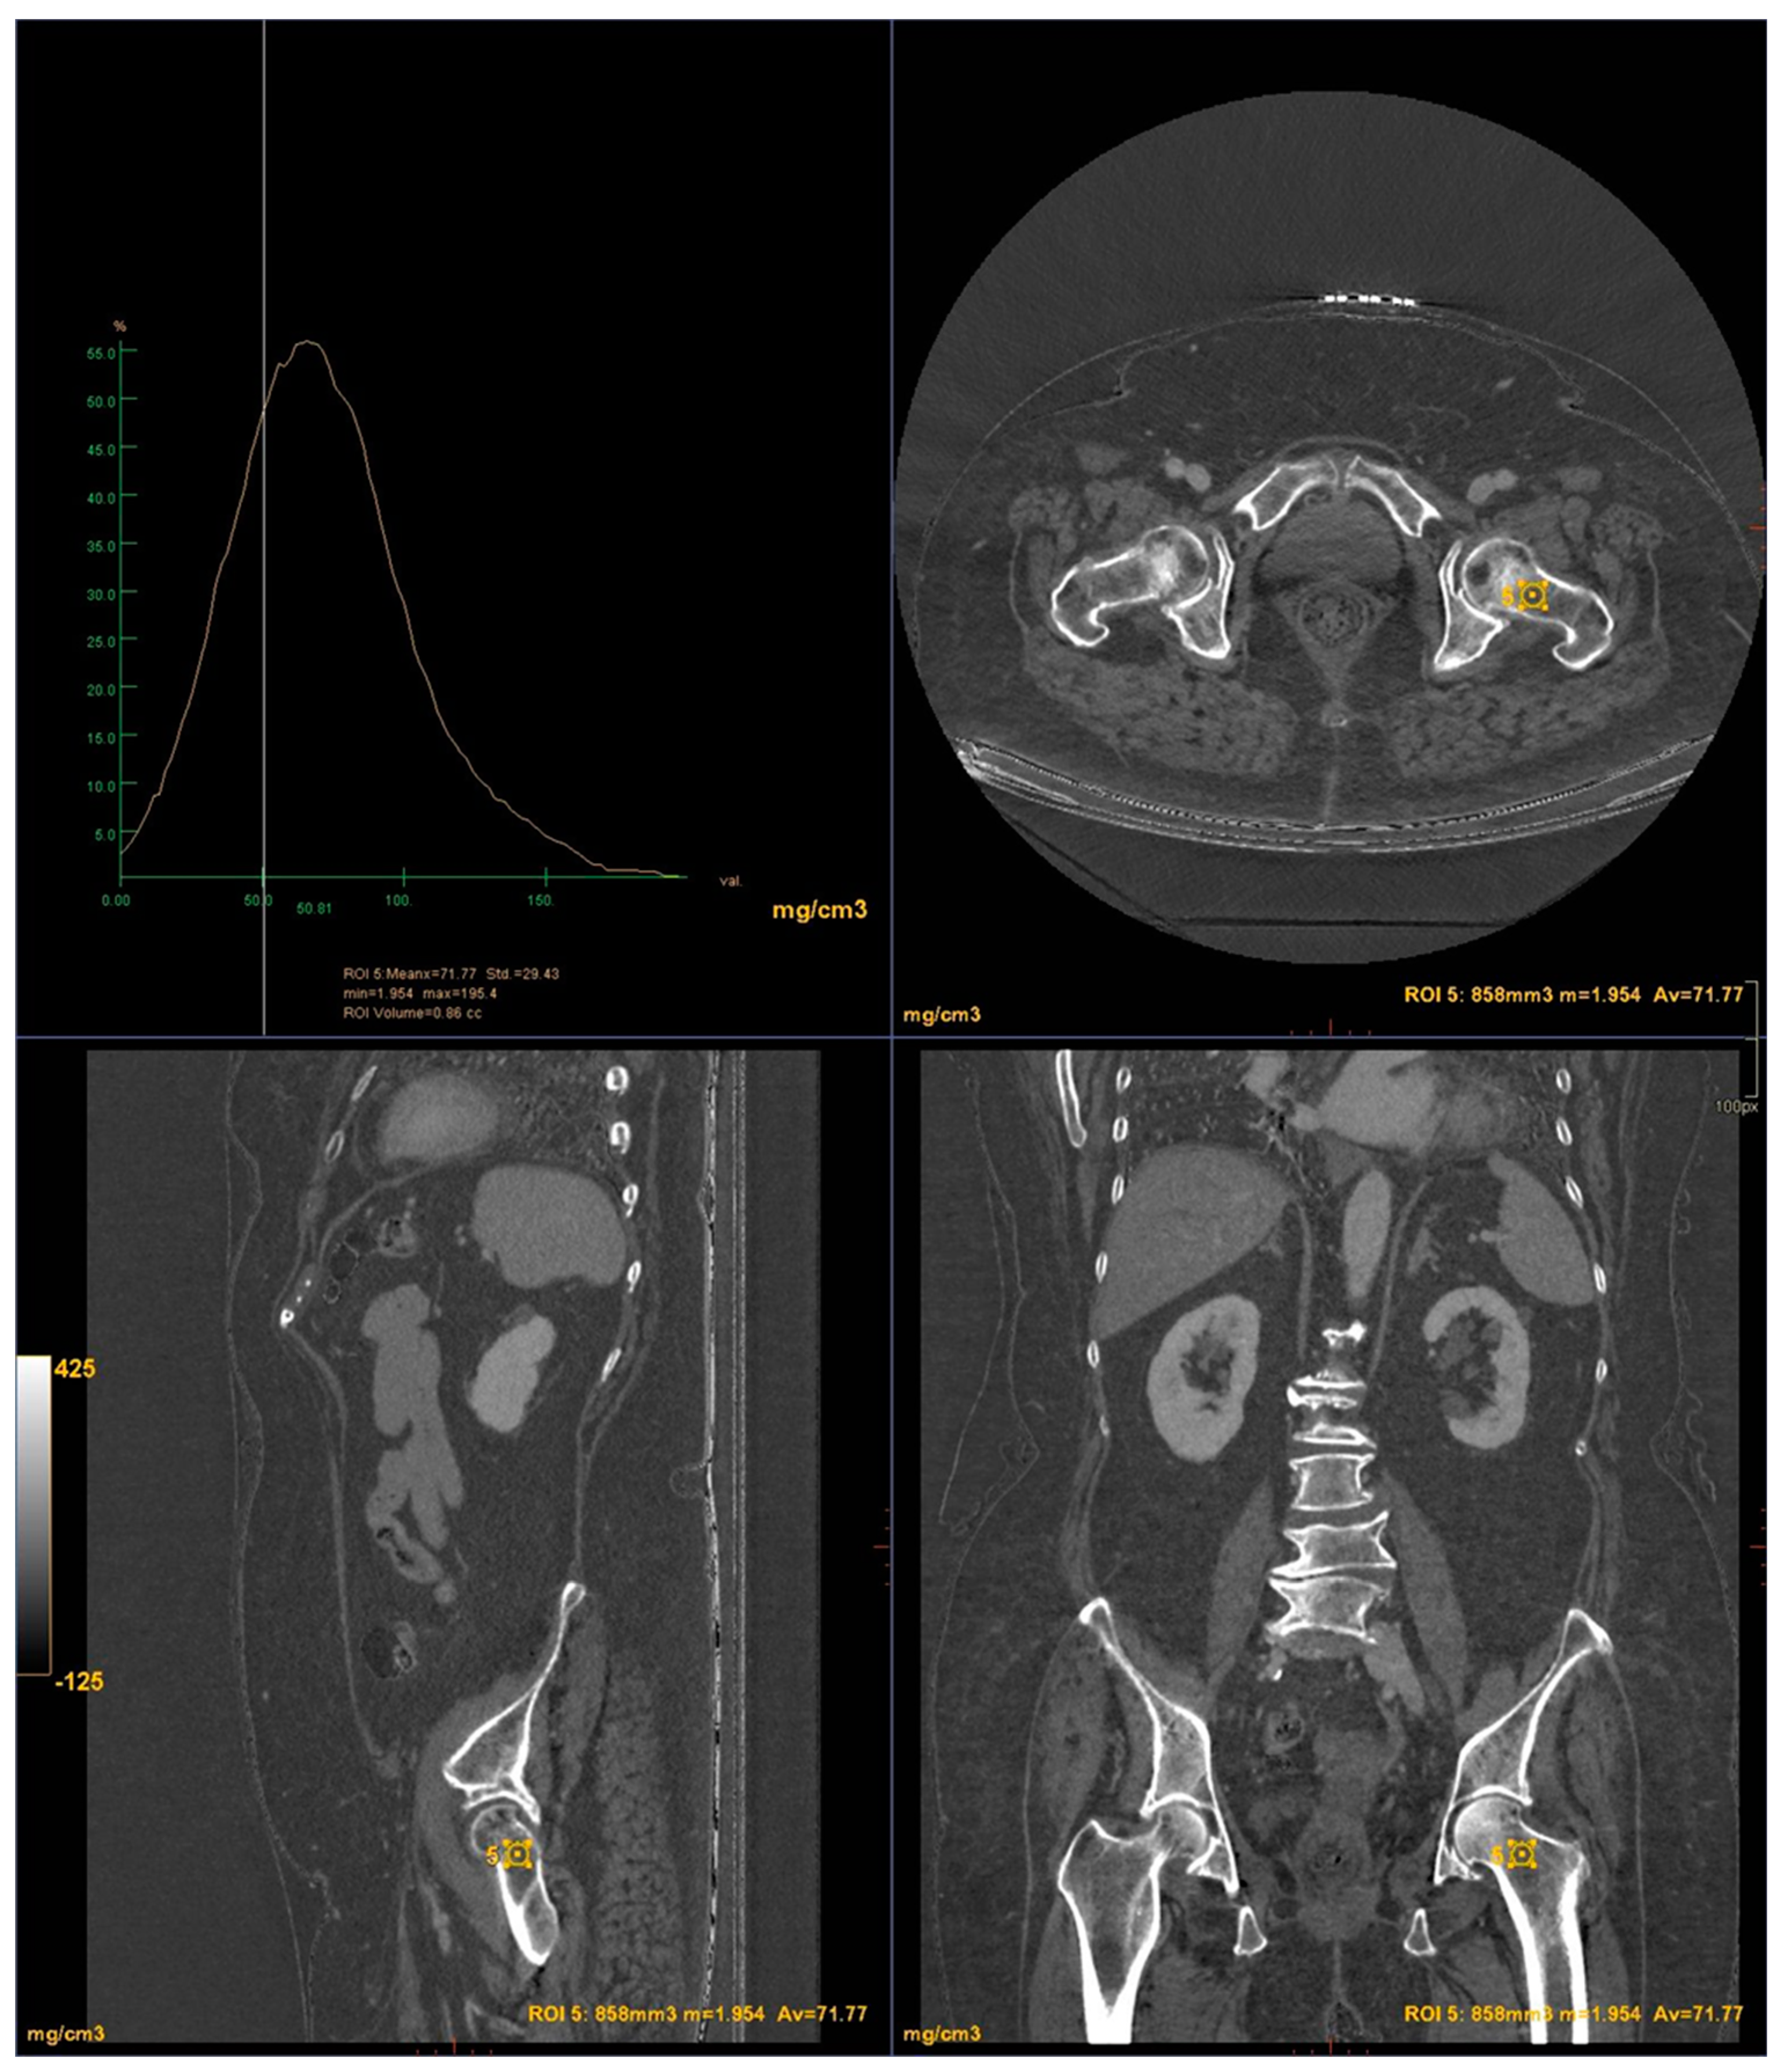

All images were acquired using a 256-slice multidetector CT system with spectral imaging capability (Revolution, GE Healthcare, Chicago, USA) using a 1.0 mm slice thickness, tube voltage of 80-140 kVp, and tube current of 200 mA (Dose Right automatic exposure control system). The CT data were reconstructed with GSI data, and MPR reconstructions were performed in coronal and sagittal planes. DXA scans were performed using a bone densitometer (Discovery A, HOLOGIC, USA) for the lumbar vertebrae (L1 to L4) and femoral neck (Figure 1 and Figure 2).

CT images were processed using AW3.2 software (GE Healthcare, USA) with a bone window and HAP(fat) reconstruction filter, which highlights structures containing hydroxyapatite. Three-dimensional volume of interest (VOI) measurements were taken at the lumbar vertebrae (Figure 3) and femoral neck (Figure 4), sampling the trabecular bone while excluding cortical bone regions.

Figure 4. DECT measurements on the femoral neck.

For the femoral neck the mean BMD and T-score on DXA images were 0.522 g/cm2 and -2.92 for the osteoporosis group, 1.19 g/cm2 and -1.7 for the osteopenic group and 1.98 g/cm2 and -0.68 for the normal group, respectively (Figure 7). There was a significant difference among the osteoporosis, osteopenic and normal groups in BMD and T-score (all p < 0.001). The mean HAP value on DECT images was 74.71 mg/cm3 for the osteoporosis group, 107.57 mg/cm3 for the osteopenic group and 121.93 mg/cm3 for the normal group (p < 0.001) (Table 2). Bland-Altman analysis revealed a bias of 0.11, with 95% limits of agreement from −1.2 to 1.4 (p = 0.2) (Figure 8).

An inverse correlation was observed between T-score and DECT HAP(fat) measurements on the lumbar vertebrae (R2: -0.042; RMSE: 0.690). In contrast, a good linear relationship was found between T-score and DECT HAP(fat) measurements on the femoral neck (R2: 0.341; RMSE: 0.589).